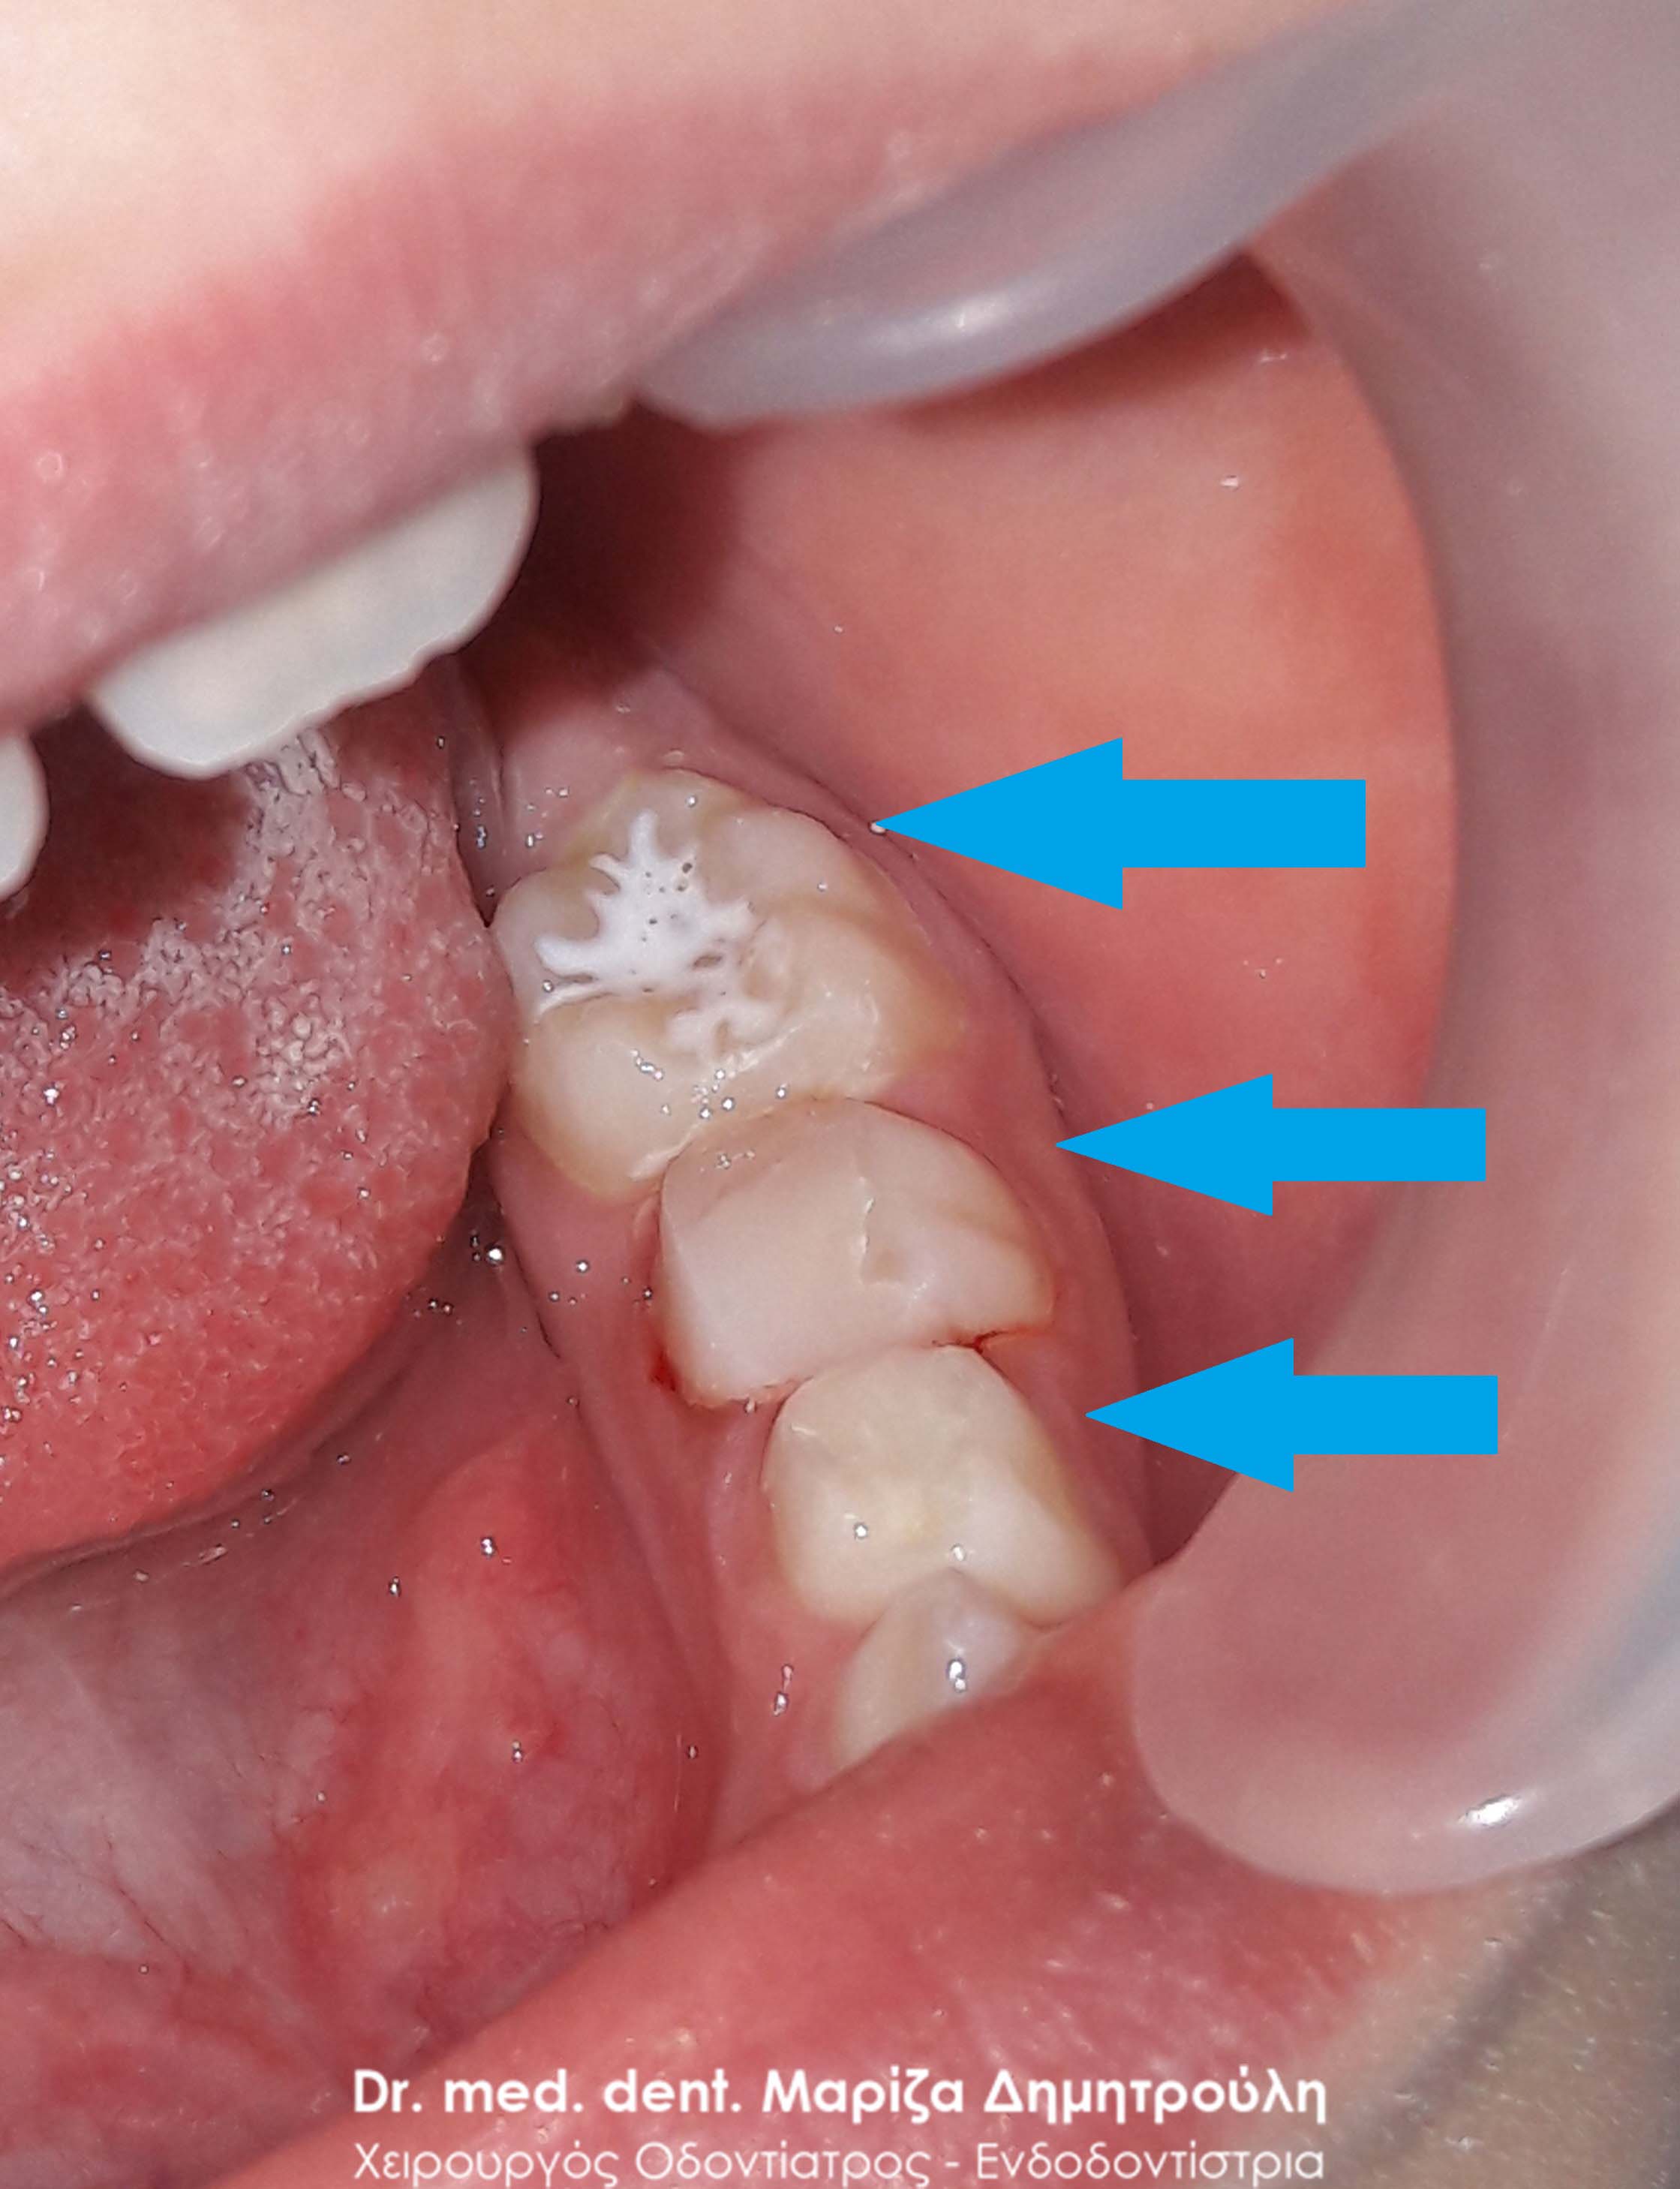

Κορίτσι ηλικίας 9 ετών αναφέρει οτι πονάει στην πάνω αριστερή πλευρά του στόματος της όταν μασάει. Μετά την κλινική εξέταση διαπιστώθηκε η ύπαρξη 2 τερηδονισμένων δοντιών. Στον πρώτο μόνιμο αριστερό γομφίο είναι εμφανής η ύπαρξη τερηδόνας, της οποίας η έκταση αποδείχτηκε αρκετά βαθιά κατά τη διάνοιξη του δοντιού. Στο δεύτερο νεογιλό (παιδικό) γομφίο παρατηρήθηκε η ύπαρξη τερηδονικής κοιλότητας μεσαίου βάθους.

Μετά την απομάκρυνση της τερηδόνας από τα δύο δοντάκια πραγματοποιήθηκαν λευκά σφραγίσματα σύνθετης ρητίνης.

ΠΡΙΝ

ΜΕΤΑ